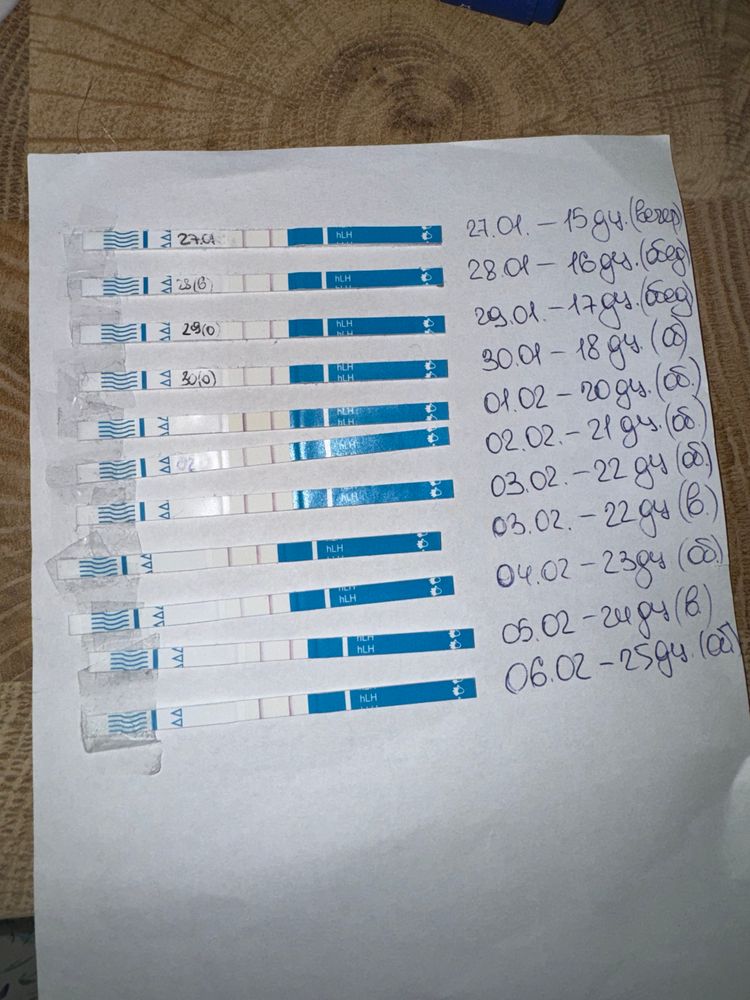

Овуляция была или ещё будет?

Как думаете, овуляция была уже? Если да, то на какой дц?

1 февраля тест положительный,значит была 1-3 февраля

Наталья, а почему тогда не снижается ЛГ, не знаете? На сколько я знаю, то должно снижаться.. вот Фемометр мне показывает сегодня пик🫠

Elena Krushelnytskaya, а от 1 числа что фемометр говорит?там самый яркий тест

Наталья, от первого тоже говорил пик, и тоже 200%🤔

я ради интереса несколько циклов после родов делала тесты на овуляцию, то после пика тесты тускнели.

Наталья, поэтому я и думаю что странный цикл, странные тесты, графики - не перерос ли фоликул в кисту. А то такое ощущение, что овуляция вот-вот наступит и не наступает (по тестах и графику). А вот симптомы все второй фазы (выделения, боль в груди, аппетит, усталость, головная боль)

раньше на 17-19 дц ловила пик